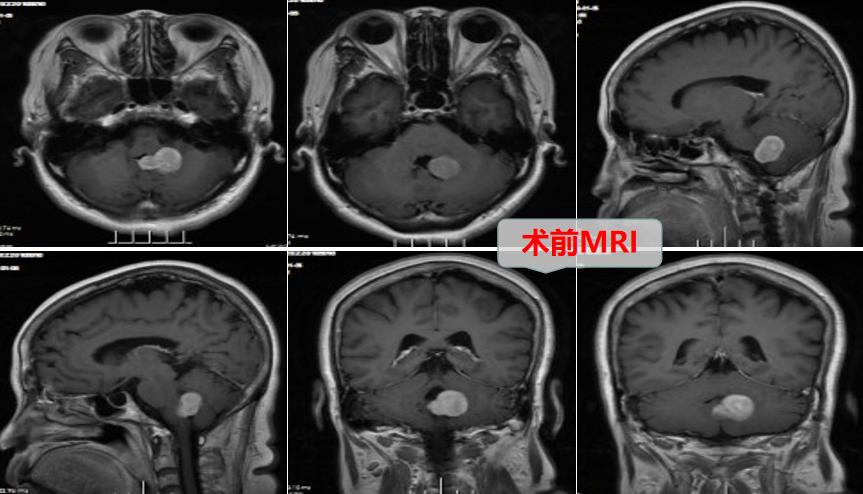

我院神经外十科主任欧阳辉教授接诊了患者。患者MRI检查结果提示:左侧小脑半球-蚓部示大小约27mmx19mmx25mm的团块,这是导致患者出现走路歪斜的主要原因。结合患者的症状,欧阳辉教授考虑患者颅内肿瘤是良性脑膜瘤的可能性比较大。

欧阳辉教授带领团队对患者的病情进行了详细讨论,最终决定对患者行“左侧小脑半球、蚓部-四脑室肿瘤切除术”。

术中可见肿瘤质韧,边界清晰,位于左侧小脑半球至小脑蚓部达四脑室。神经外十科团队在高清显微镜下,精准仔细操作,顺利全切肿瘤。术后病理确诊脑膜瘤。欧阳辉教授解析,考虑为四脑室出口处脉络丛或蛛网膜起源的良性脑膜瘤,生长突入四脑室并挤压左侧小脑半球,此种情况的脑膜瘤临床较少见。